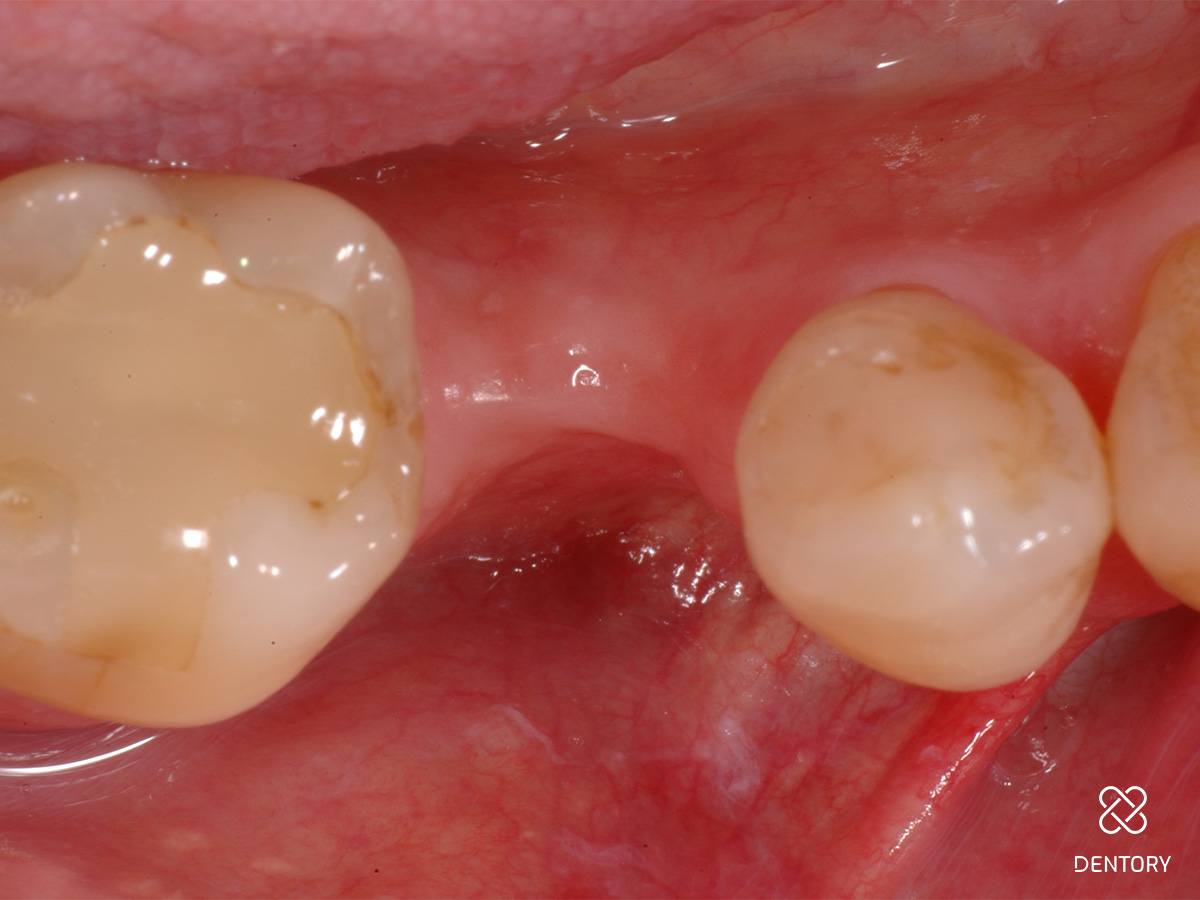

Abbildung 1

Ausgangssituation: Einzelzahnlücke regio 35.